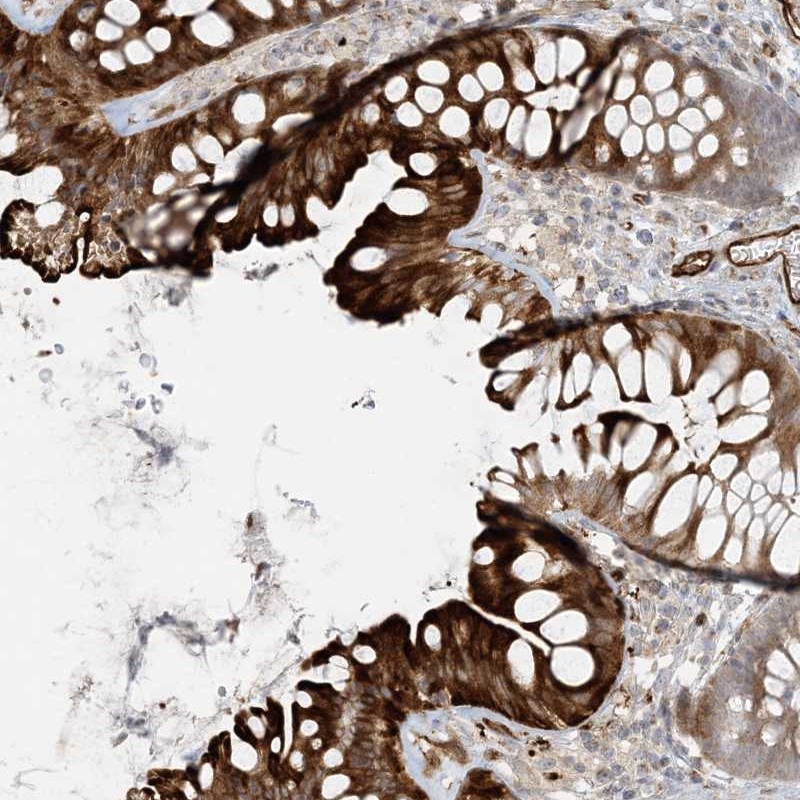

Immunohistochemical staining of human colon shows strong cytoplasmic and membranous positivity in glandular cells.